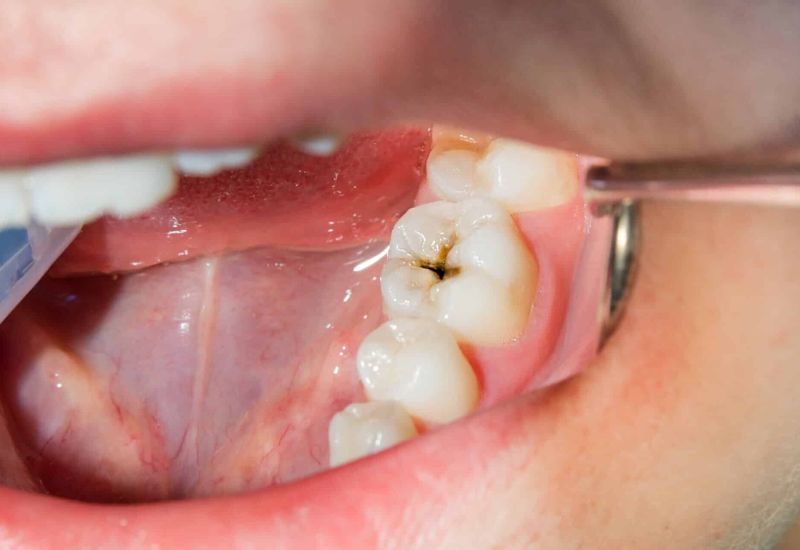

Nguyên nhân phổ biến nhất được ghi nhận trong các tài liệu của Trung tâm Kiểm soát và Phòng ngừa Dịch bệnh Hoa Kỳ (CDC) là nhiễm trùng từ răng số 6, 7, 8 hàm dưới, đặc biệt khi sâu răng hoặc viêm quanh chóp không được điều trị triệt để.